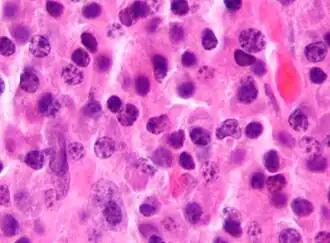

Морфология

Опухолевая ткань разрастается преимущественно в плоских костях (череп, рёбра, таз) и в позвоночнике, инициируя в них остеолизис[6] и остеопороз. На рентгенограмме очаги поражения имеют вид гладкостенных пробоин. Полости образуются в местах роста миеломных клеток за счёт активации ими остеокластов, осуществляющих лизис и резорбцию костной ткани («пазушное» рассасывание). Помимо костного мозга, опухолевые инфильтраты могут обнаруживаться и в других органах.